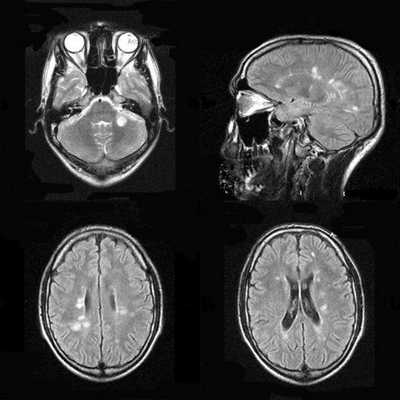

МРТ головного мозга играет ключевую роль в выявлении, оценке распространения и прослеживания динамики герпетического энцефалита. При МРТ головного мозга типичные черты герпетического энцефалита: высокий сигнал от височной доли на Т2-взвешенных МРТ, чаще одностороннее поражение. Поскольку эта зона на МРТ соответствует области Вернике, то у пациента наблюдается афазия и другие речевые расстройства. На МРА нарушений проходимости сосудов не отмечается. МРТ в СПБ при герпетическом энцефалите проводится как в условиях стационара при тяжелом состоянии, так и амбулаторно, в том числе в открытом МРТ. Центры МРТ СПб не имеющие опыта МРТ головного мозга при инфекционных заболеваниях нередко принимают их за опухоли, что ведет к неверной тактике лечения.

МРТ головного мозга. Аксиальная Т2-взвешенная МРТ. Герпетический энцефалит.

МРТ головного мозга. Тот же пациент. Аксиальная Т1-взвешенная МРТ с контрастированием.

При герпетическом энцефалите на МРТ характерно поражение медиальной области височных долей, нижней поверхности лобных долей и островковой коры. Реже вовлекается корковое вещество затылочных долей, поясная извилина. Иногда поражается конвекситальная поверхность полушарий мозга. На ДВИ определяют ограничение диффузии среди элементов лимбической системы.

Для наиболее раннего выявления энцефалита рекомендуют выполнение мультипланарной МРТ в режиме Т2-ВИ, FLAIR или ДВИ, исследование с контрастом в режиме Т1-ВИ. При этом изменения на МРТ обнаруживают раньше, чем на КТ на 1 - 2 суток. Также на МРТ изображениях больше видны последствия кровоизлияний спустя 7 дней от появления симптомов.

МРТ в 90 % случаев выявляет ранние частые признаки герпетического энцефалита - симметричное поражение медиальных областей теменной доли с преимущественным поражением серого вещества. Это помогает вовремя поставить диагноз, назначить правильное лечение, спасти жизнь больного и уменьшить риск осложнений.